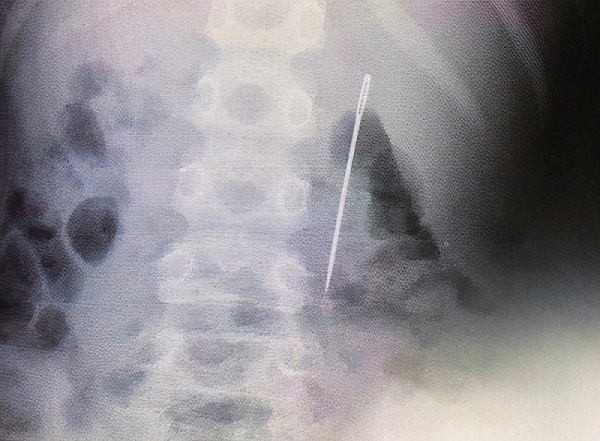

Sự việc xảy đến với cậu bé Hạo Hạo (8 tuổi, sống tại Trú Mã Điếm, Hà Nam, Trung Quốc). Cụ thể, thấy Hạo Hạo bị đau bụng bất thường, gia đình nhanh chóng đưa em đến Bệnh viện Nhi Hà Nam để kiểm tra. Qua quá trình thăm khám, các bác sĩ phát hiện một cây kim dài khoảng 6cm nằm trong tá tràng, bên phải khoang bụng của Hạo Hạo.

Bé trai 8 tuổi vô tình nuốt phải cây kim dài khoảng 6cm. |

Các bác sĩ đã sử dụng phương pháp nội soi để tìm gắp dị vật. Vào thời điểm đó, chiếc kim đã nằm ở giữa tá tràng. Ca phẫu thuật được thực hiện thành công. Cậu bé chưa bị thủng ruột tuy nhiên, những vết loét đã bắt đầu hình thành.